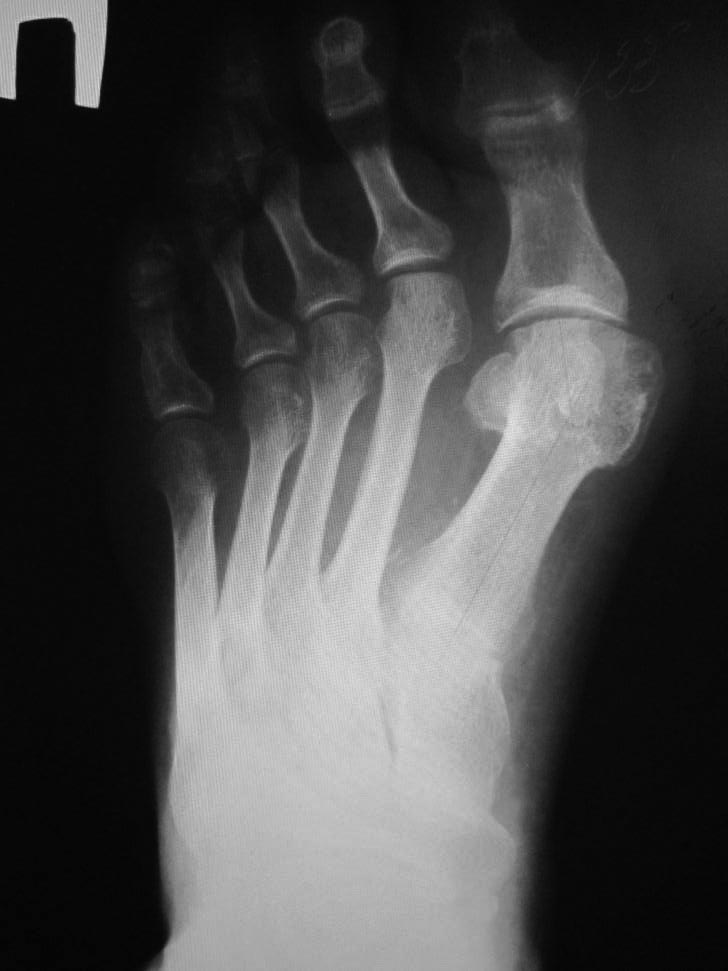

Hallux valgus+грибковое поражение 2 пальца

Больной 67 лет обратился с просьбой удалить 2 палец, так как уже целый год испытывает сильные боли в области 2 пальца при ходьбе.

Лечение у дерматолога оказалось не эффективным. Вальгусная деформация 1 пальца стопы беспокоит тоже пациента, но в гораздо меньшей степени.Уважаемые коллеги - подскажите наиболее разумную тактику лечения.

Первое, что бросается в глаза- явно удлиненная 2 плюсневая кость. Может все-таки боли связаны с молоткообразной деформацией 2 пальца? Возможно стоит рассмотреть такой план- SCARF на 1 луче, укорачивающая остеотомия на 2 луче, остеотомия основной фаланги 2 пальца, тенотомии сгибателей 2 пальца. Ну и в конце удалить ногтевую пластинку 2 пальца.

Согласен с Александром - удлинение 2 луча - очевидно. Палец упирался в обычную (дешёвую) обувь (если присмотреться - контур, по пальцам, в виде правильного овала, скорее всего носил "керзачи" или что-то подобное), вызывая неприятные болезненные ощущения при ходьбе. С этим всё связано. Микотическое поражение стоп у 80% больных с вальгусной деформацией и плоскостопием, клинические проявления скудные, в лёгких случаях онихомикоз и межпальцевой дерматит или другие проявления (лихинефикация. оккантолиз, могут быть пустулы в кожных покровах стопы....).

Согласен с коллегами. Греческий тип стопы - вполне возможная причина болей. Плюс - формирующаяся молоткообразная деформация второго пальца, в т.ч., связанная с постепенным разрывом подошвенной пластинки второго плюснефалангового сустава. Период формирования разрыва может быть болезненным. Вероятно, нужно думать об укорочении второго луча. И устранении вальгусной деформации первого и второго (а может и других) пальцев. По рентгенограмме не очень получается оценить первый межплюсневый угол. Возможно, вмешательство на первой плюсневой кости и не нужно, если угол маленький. И достаточно будет остеотомии Akin, субкапитальной остеотомии М2 и корригирующей вальгус и укорачивающей остеотомии основной фаланги второго пальца. Не очень понятным остается отек стопы.